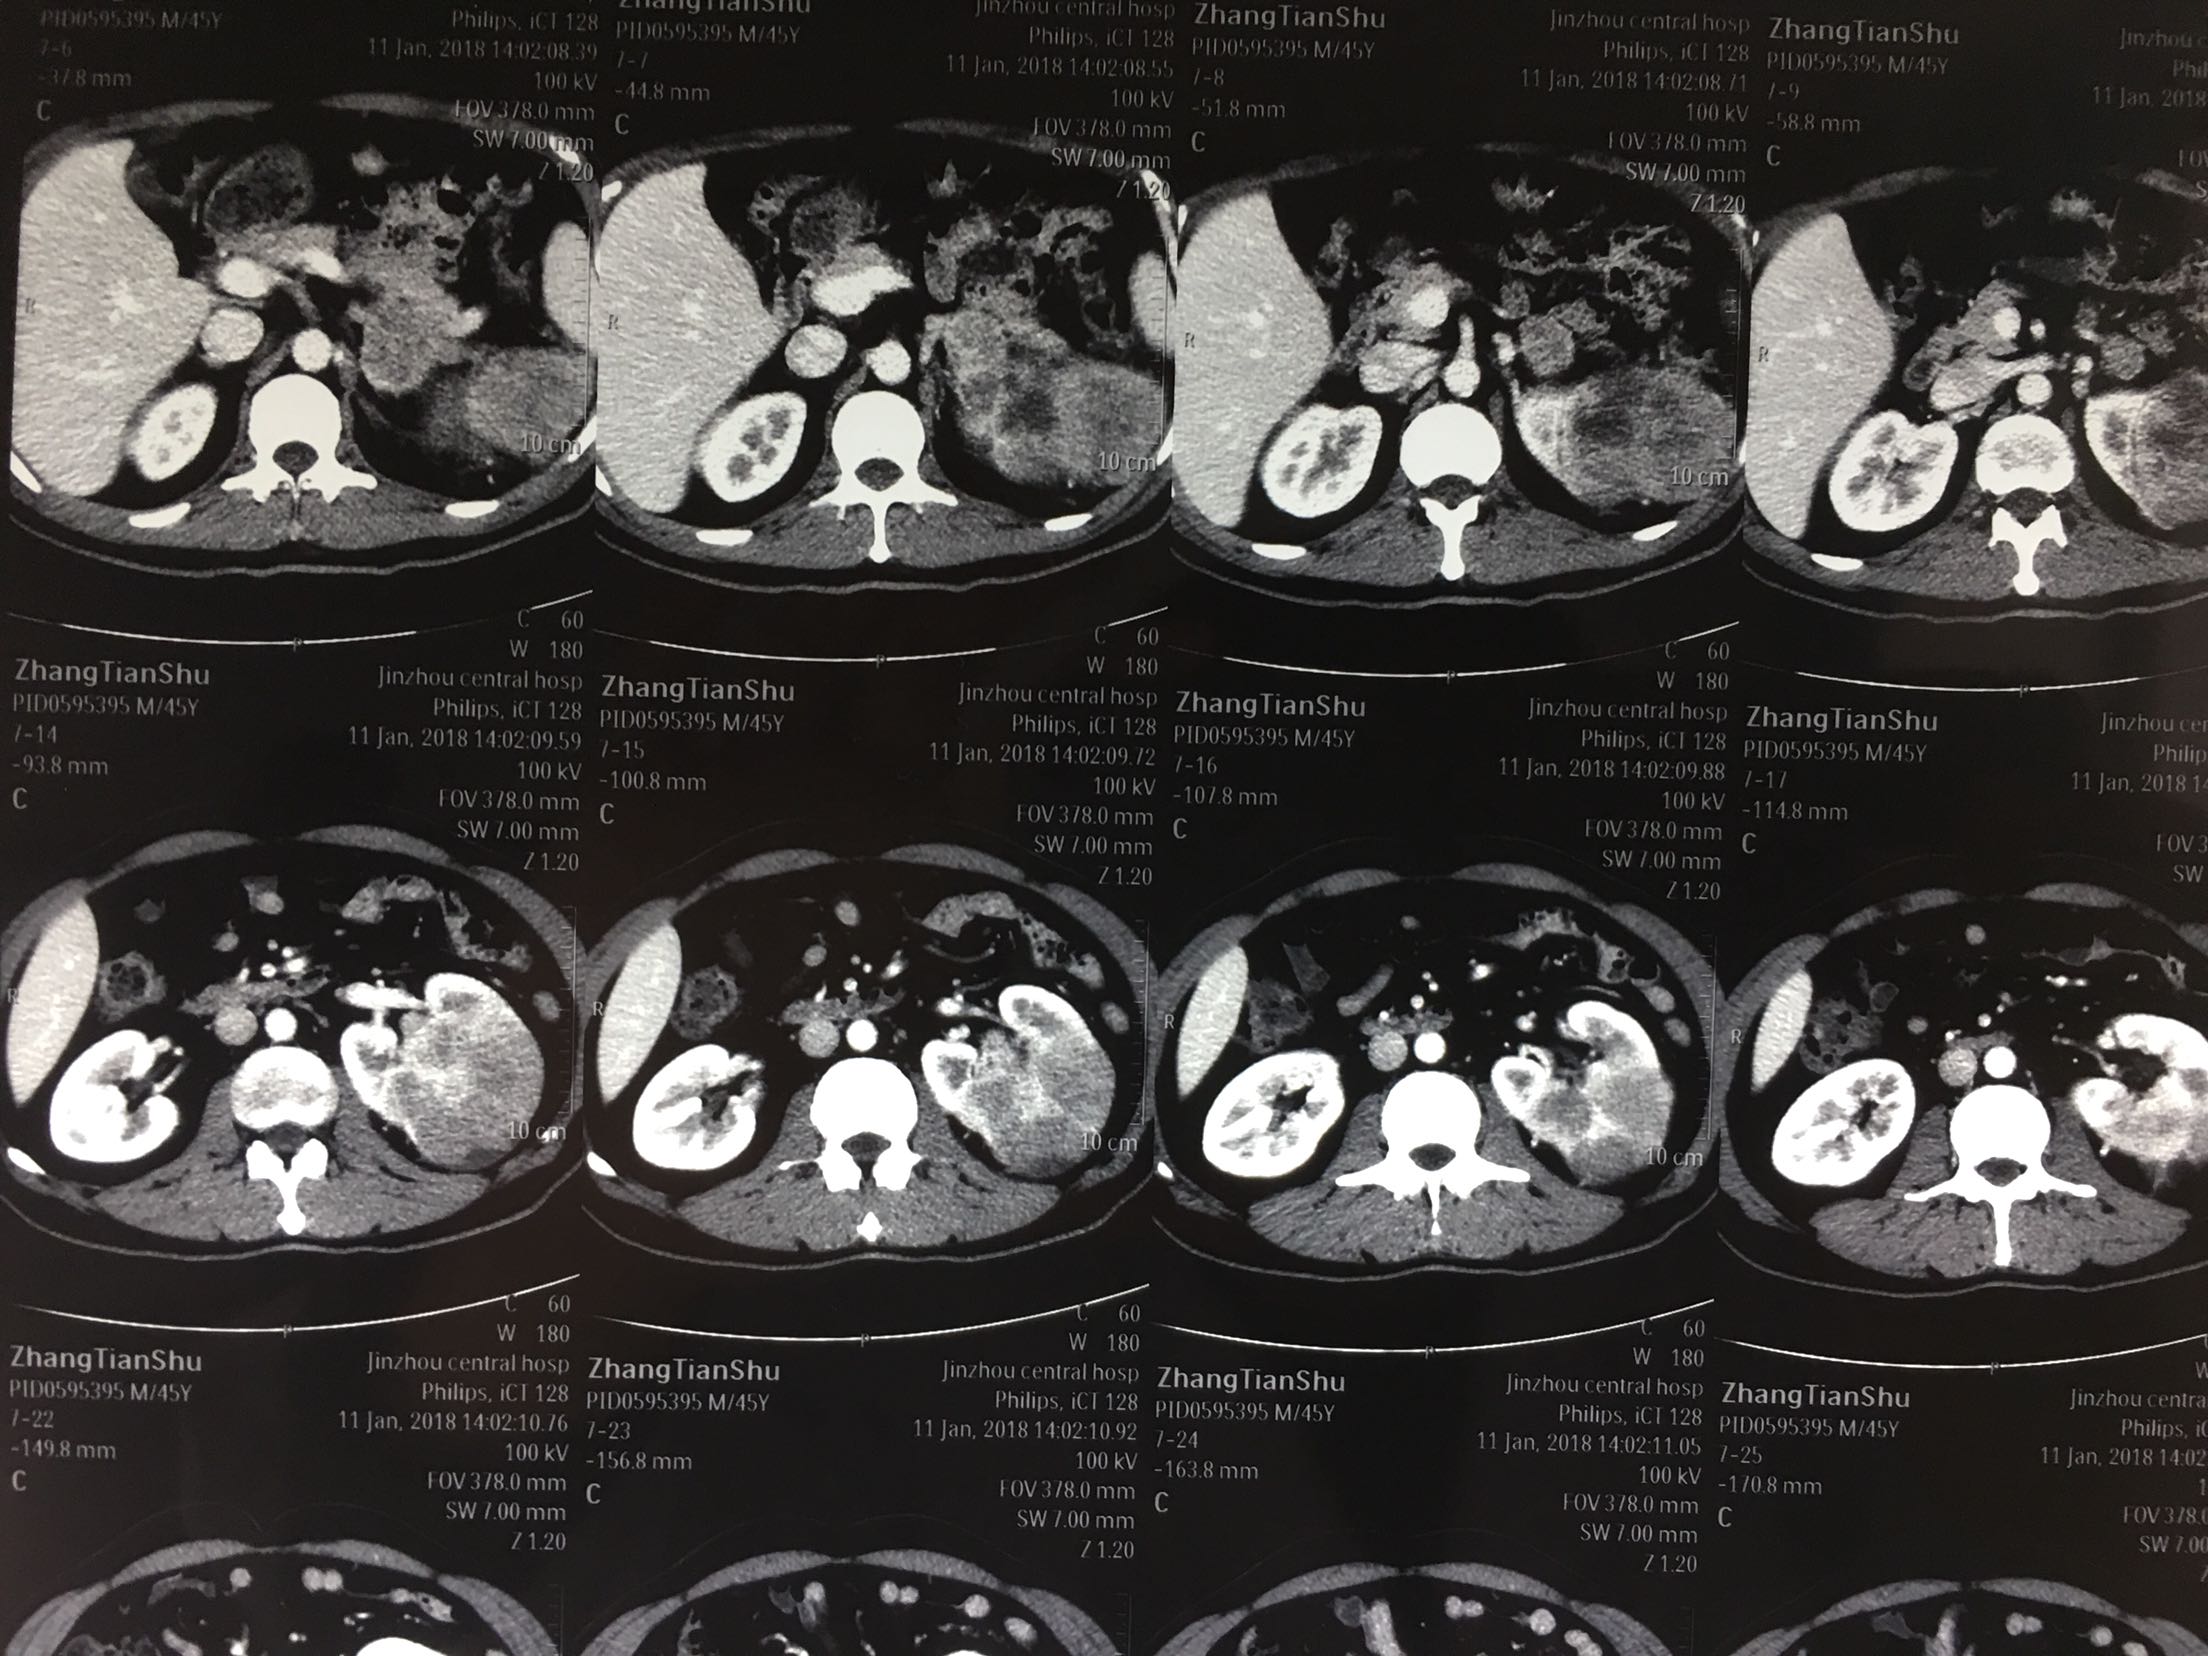

查体:左肾区轻叩击痛,双输尿管走形区无压痛,耻骨上区无隆起及压痛, 辅助检查:泌尿系彩超:左肾肿瘤。 ctu:左肾癌伴同侧肾上腺侵犯。

诊断:左肾癌伴肾上腺转移 治疗:根治性左肾切除术

术后病理:左肾透明细胞癌局部肉瘤样变,肾上腺及腹膜累及。 讨论:肾脏肿瘤肉眼血尿,腰疼,腹部包块为晚期肿瘤症状,预后不良。